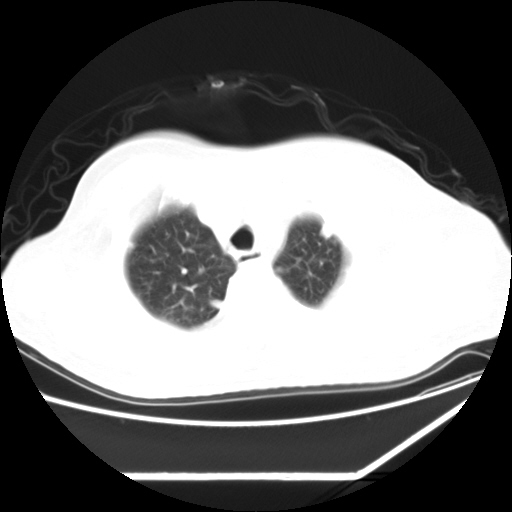

男,57,畏寒,发热

双肺多发结节样病灶,部分内见透光区,纵隔内见淋巴结肿大。结核临床如有畏寒,高热,白细胞增高首先考虑迁徙性肺脓肿(多是金黄色葡萄球菌感染)。

畏寒发热,首先考虑血源性肺脓肿,结合临床,抗炎后复查排除转移瘤等。

1)考虑两肺感染性病变(金黄色葡萄球菌肺炎?);建议抗炎治疗后复查排除其他。2)双侧少量胸腔积液。